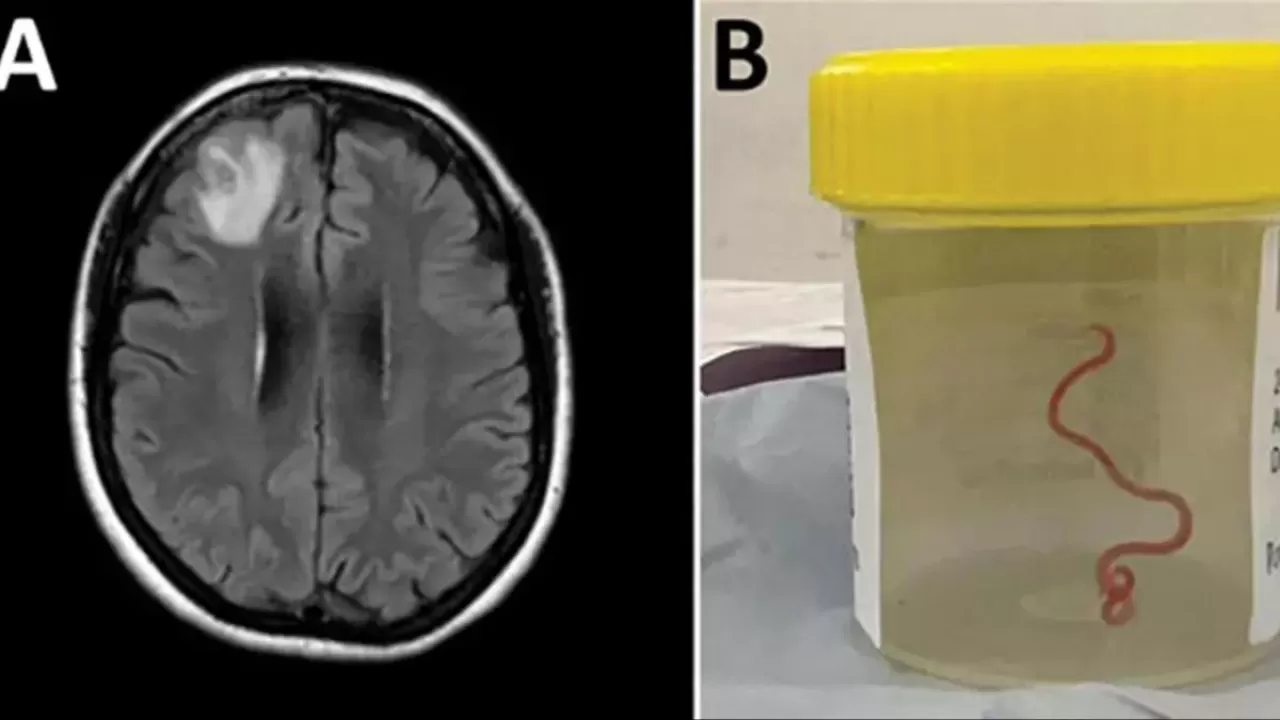

Avustralya Ulusal Üniversitesi'nden (ANU) yapılan açıklamaya göre 64 yaşındaki bir kadın karın ağrısı, ishal, kuru öksürük, ateş ve geceleri terleme şikayetleriyle ilk olarak Ocak 2021'in sonlarında hastaneye kaldırıldı. Daha sonra 2022 yılında unutkanlık ve depresyon şikayetleri de görülen kadın, Canberra Hastanesi'ne sevk edildi. MR taraması yapılan kadının, beyninin sağ ön lobunda anormallik tespit edilmesi üzerine ameliyat kararı verildi. Ameliyat sırasında doktorlar, kadının beyninde 8 santimetre uzunluğunda canlı solucan buldu. Latince adı "Ophidascaris robertsi" olan solucanın normalde piton yılanlarında bulunan bir parazit olduğu belirtildi. ANU ve Canberra Hastanesi'nin önde gelen bulaşıcı hastalık uzmanı Doçent Sanjaya Senanayake, "Bu, dünyada bir insanda görülen ile Ophidascaris vakasıdır" ifadesini kullandı.